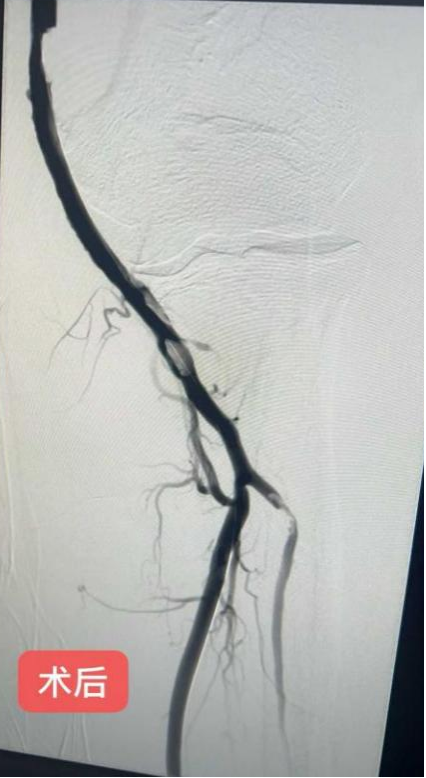

手术经右侧股动脉穿刺,将5F亲水涂层造影导管精准送至肱动脉近段。造影显示患者肱动脉血栓负荷较重,血流严重受阻,但已形成侧枝循环,为手术提供了有利条件。随后,团队实施机械血栓清除术,多次操作后血栓明显减少。为进一步改善血管通畅度,术中采用4.0mm×150mm非顺应性外周动脉血管球囊对病变段进行扩张。扩张后再次造影检查后显示,患者肱动脉病变部位扩张效果良好,血流恢复正常,手术顺利完成。

术后24小时内,医护团队密切监测患者生命体征及肢体恢复情况。令人欣慰的是,患者左臂疼痛完全消失,皮肤温度回升,各动脉搏动恢复,上肢活动自如,未遗留任何功能障碍。